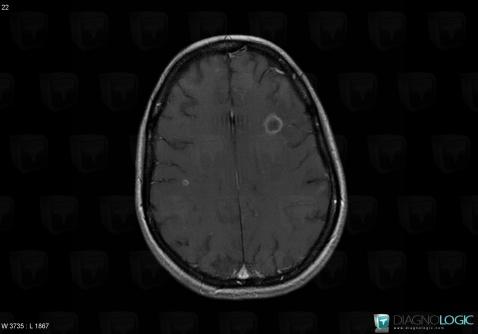

Toxoplasmosis, Cerebral hemispheres, MRI

Here is the specific information in the key image above:

- Diagnosis Toxoplasmosis (link to Abscess), Location(s) Cerebral hemispheres, with gamuts Intracerebral T2W or FLAIR hypointense lesion, Multifocal intracranial lesions